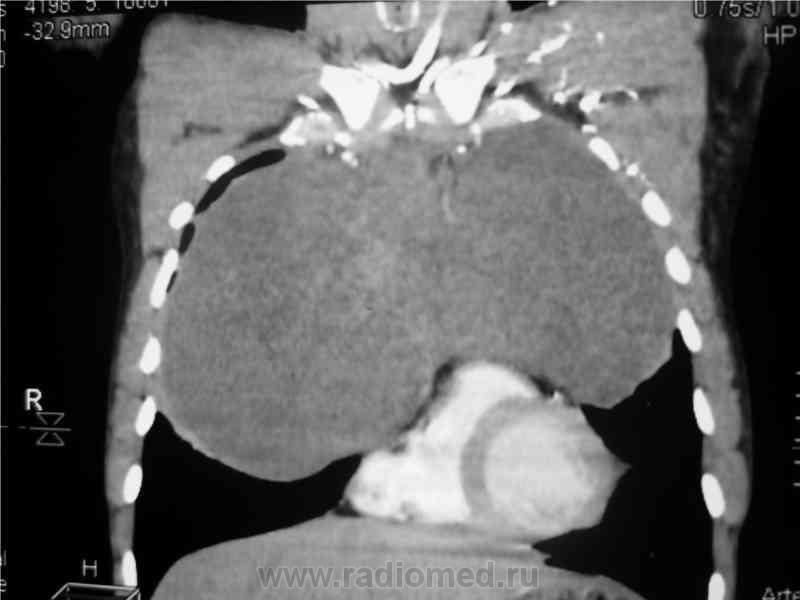

Мужчина 36 лет, рентгеногафия и КТ грудной полости.

Жалобы на субфебрильную температуру, боли в грудной клетке справа, слабость, похудание. ФГ 10 месяцев назад - норма.

КТ август 2009.

Интенсивное, однородное затемнение в средних отделах справа, слева норма - мною был заподозрен м/долевой плеврит, пациент был направлен в областной центр торакальной хирургии. Затем онкодиспансер, затем институт рака в Киеве. Результат гистологии тератобластома средостения. 2 курса химиотерапии контрольное КТ в октябре - отрицательная динамика.

Массивное неоднородное мягкотканное новообразование, исходящее из верхней или средней трети переднего средостения, оттесняет крупные сосуды вправо и кзади. По локализации должна быть злокачественная тимома. Хотя и лимфому наверное, не стоит отбрасывать, Ходжкинская маловероятна.